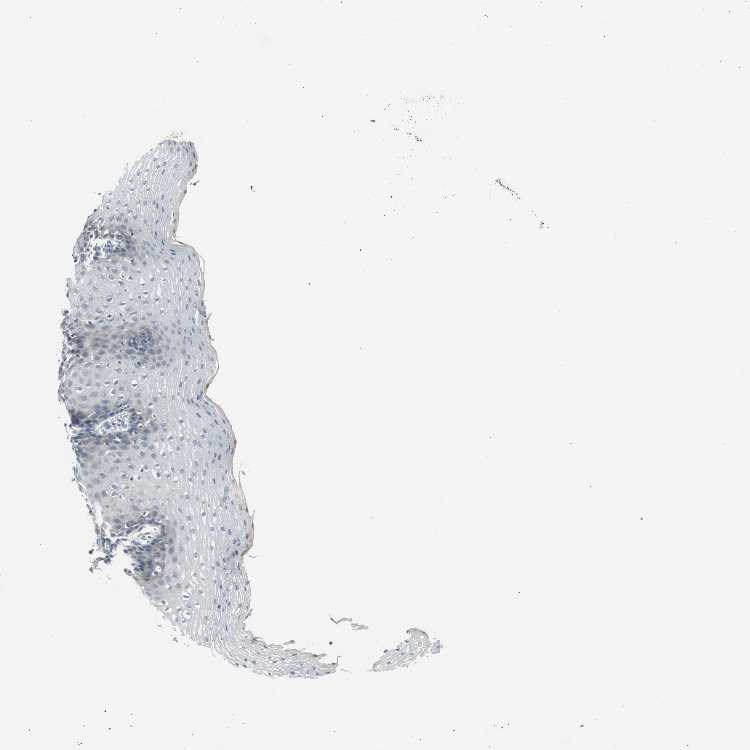

ESOPHAGUS - Antibody stainingi

Antibody staining in the annotated cell types in the current human tissue is reported as not detected, low, medium, or high, based on conventional immunohistochemistry profiling in selected tissues. This score is based on the combination of the staining intensity and fraction of stained cells.

Each image is clickable and will lead to virtual microscopy that enables deeper exploration of all samples and also displays staining intensity scores, fraction scores and subcellular localization as well as patient and tissue information for each sample.

Antibody HPA020994Antibody HPA020996Antibody CAB005035

Squamous epithelial cells LowNot detectedNot detected